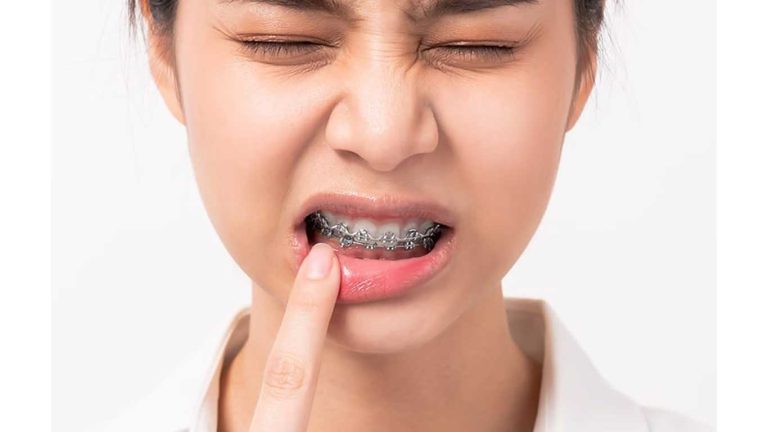

- باور غلط: ارتودنسی در بزرگسالی بسیار دردناک است. واقعیت: اگرچه مقداری ناراحتی پس از نصب و تنظیم دستگاه ها طبیعی است، اما این درد معمولا خفیف و قابل کنترل است. این درد تفاوت چشمگیری با درد تجربه شده توسط نوجوانان ندارد.